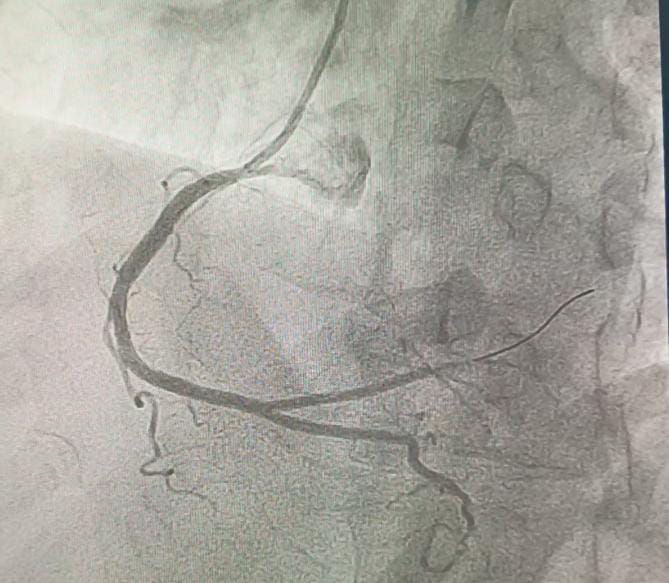

Coronary angiography revealed total occlusion of the proximal LCx and a sub totally occluded RCA with thrombus.

Both RCA and LCx were considered as the culprit lesion. We decided to addressed the lesion in RCA first, since the flow is still TIMI III. RCA was engaged with 6F JR guiding catheter. Run through wire was advanced distally to RCA. After pre dilatation with NC balloon 3.5 / 18 mm the thrombus disappeared. A 3.5 / 22 mm stent was implanted in RCA at 18 atm. Post dilatation with stent balloon at maximum pressure 20 atm. Final angiogram showed TIMI 3 flow. Then we intervene the LCx. We used BL guiding catheter to engage the LCx. Run through NS floppy wire was advanced to distal LCx. Coronary angiogram showed good contrast flow to distal LCx. Pre dilatation at proximal LCx with NC balloon 3.5 / 18 mm at 18 atm. DES was implanted at LCx at 20 atm. We did post dilatation at LCx with NC balloon up to 24 atm. Final angiogram showed TIMI III flow.